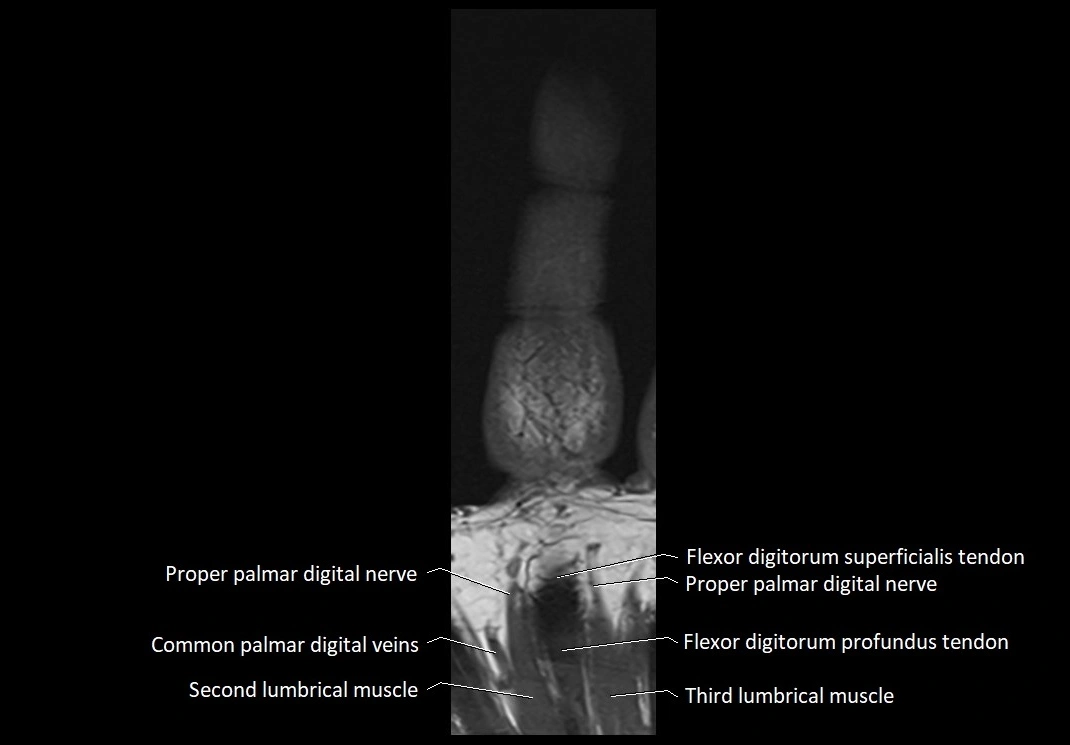

- Flexor digitorum profundus tendons

- Flexor digitorum superficialis tendons

- Proper palmar digital nerve (hand)

- Proper palmar digital nerves

- Second lumbrical muscle of hand

- Third lumbrical muscle of hand